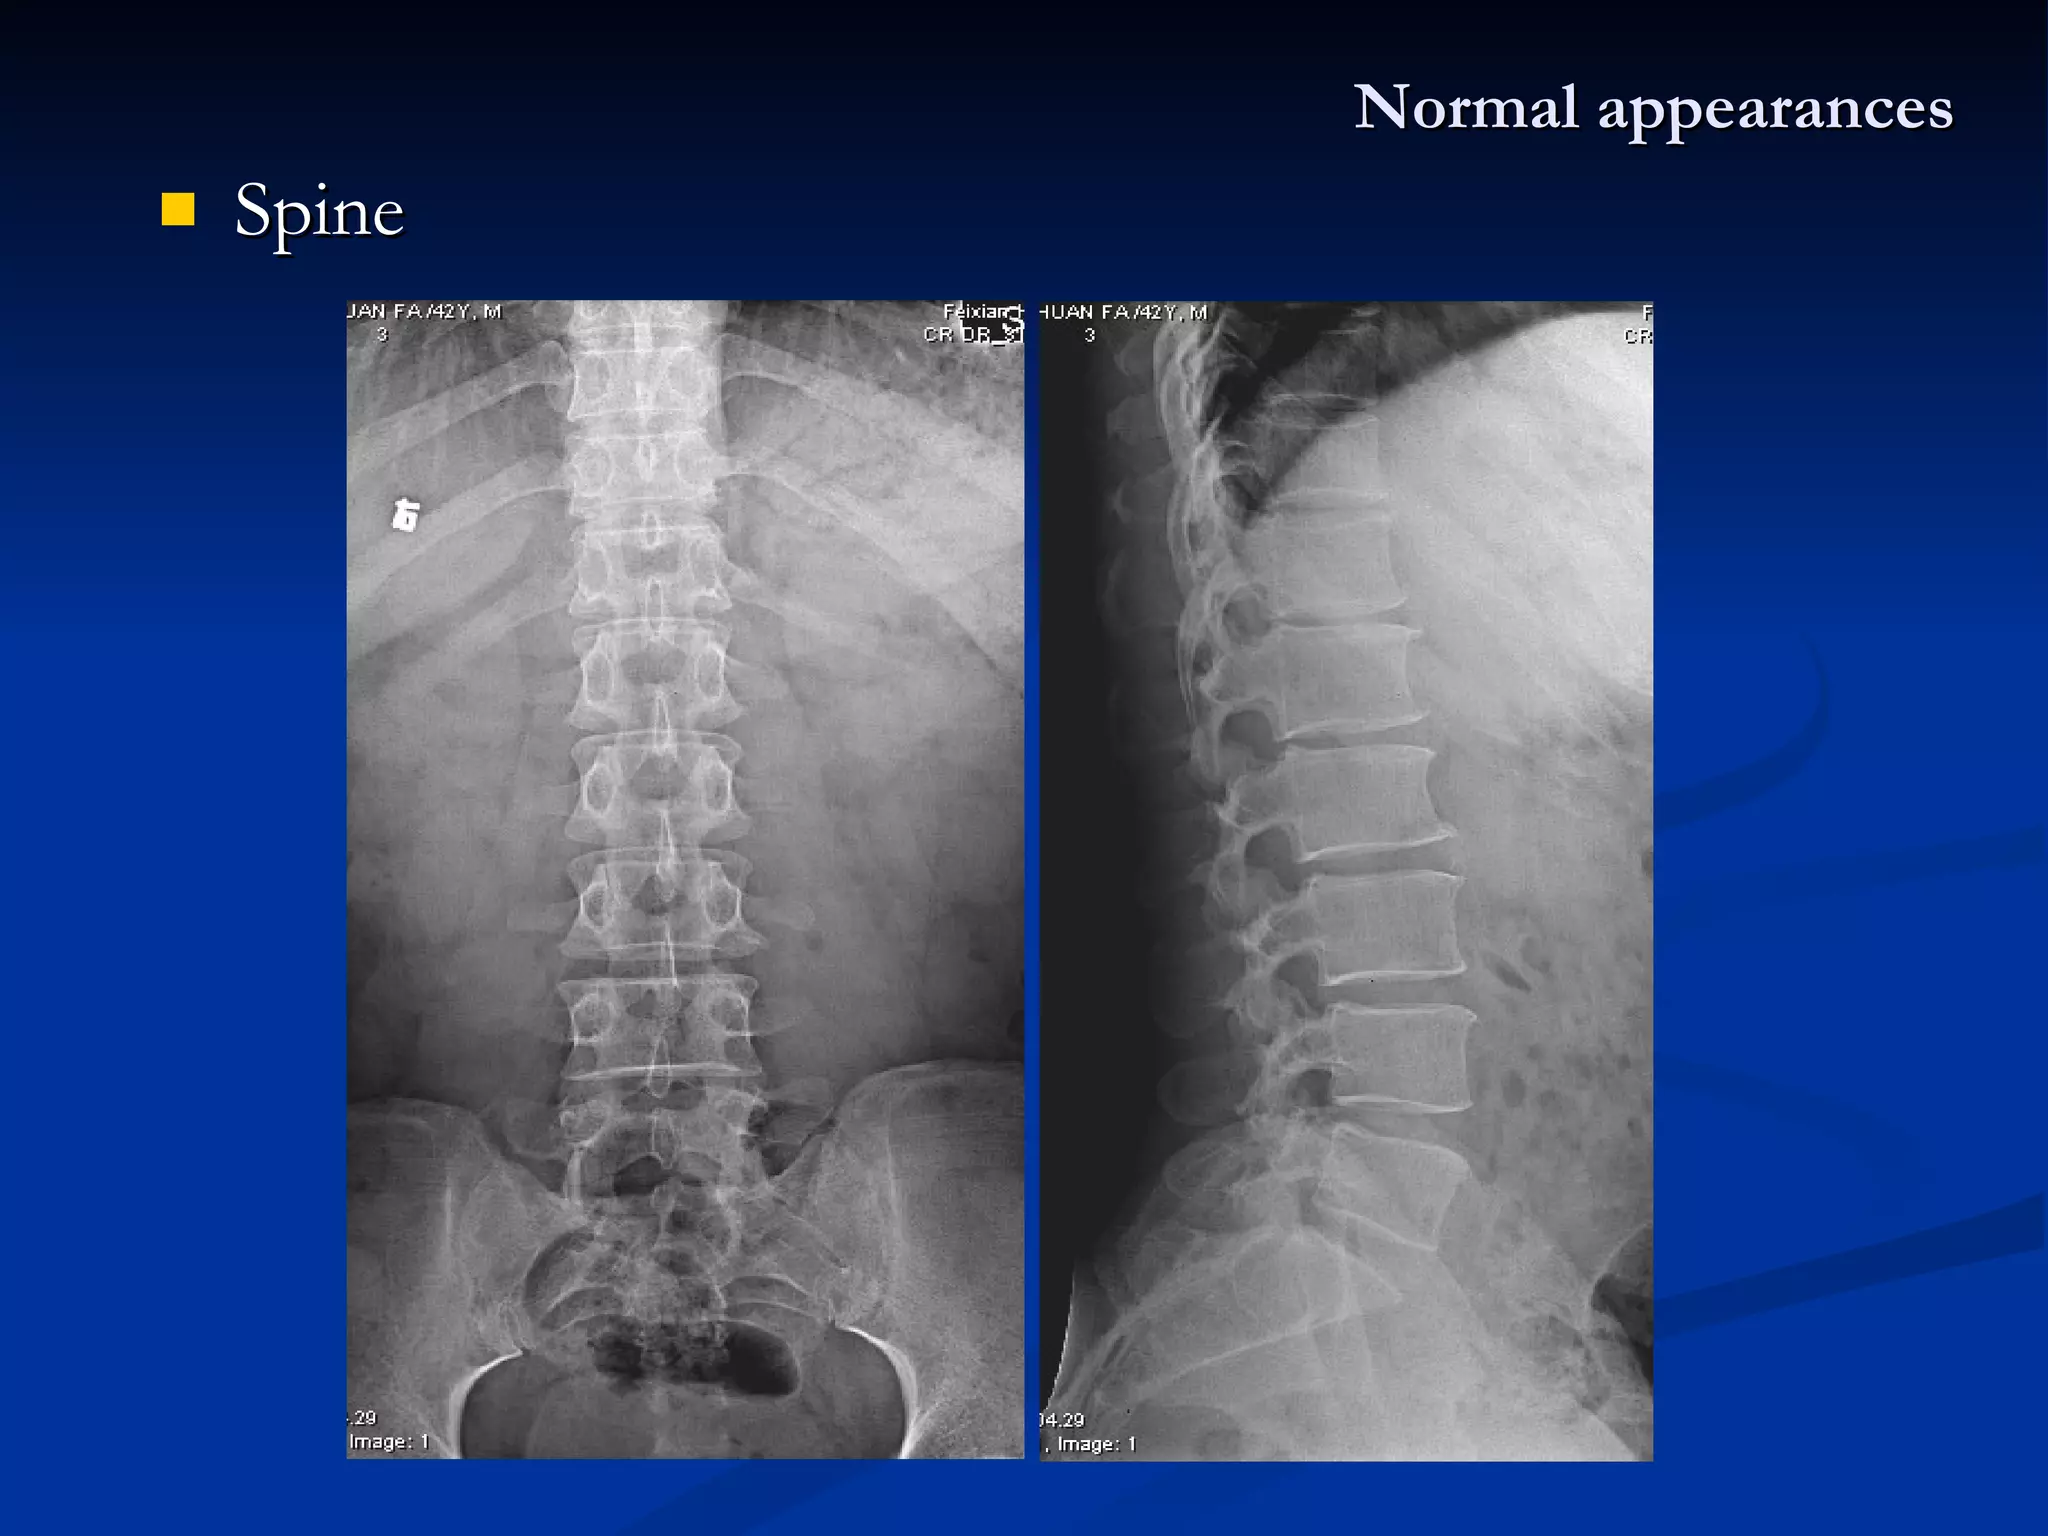

X-ray : Fracture line : the break of bone shows a irregular translucent line (separated  –  translucent overlap - dense) Transverse fracture / oblique fracture / spiral fracture Compression / crush fracture Comminution fracture ( > 2) / segmental fracture Incomplete fracture :  Fracture in children Greenstick fracture :  Epiphyseal separation fracture & dislocation  Trauma

X-ray : Fracture line : the break of bone shows a irregular translucent line Transverse fracture / oblique fracture / spiral fracture Comprese fracture Comminution fracture ( > 2) / segmental fracture Incomplete fracture :  Fracture in children Greenstick fracture :  Epiphyseal separation fracture & dislocation  Trauma angling or buckling of the cortex without the lucent fracture line Epiphysis & cartilage plate separated from the metaphysis

X-ray : Fractureline : the break of bone shows a irregular translucent line (separated – translucent overlap - dense) Transverse fracture / oblique fracture / spiral fracture Compression / crush fracture Comminution fracture ( > 2) / segmental fracture Incomplete fracture : Fracture in children Greenstick fracture : Epiphyseal separation fracture & dislocation Trauma

X-ray : Fractureline : the break of bone shows a irregular translucent line Transverse fracture / oblique fracture / spiral fracture Comprese fracture Comminution fracture ( > 2) / segmental fracture Incomplete fracture : Fracture in children Greenstick fracture : Epiphyseal separation fracture & dislocation Trauma angling or buckling of the cortex without the lucent fracture line Epiphysis & cartilage plate separated from the metaphysis